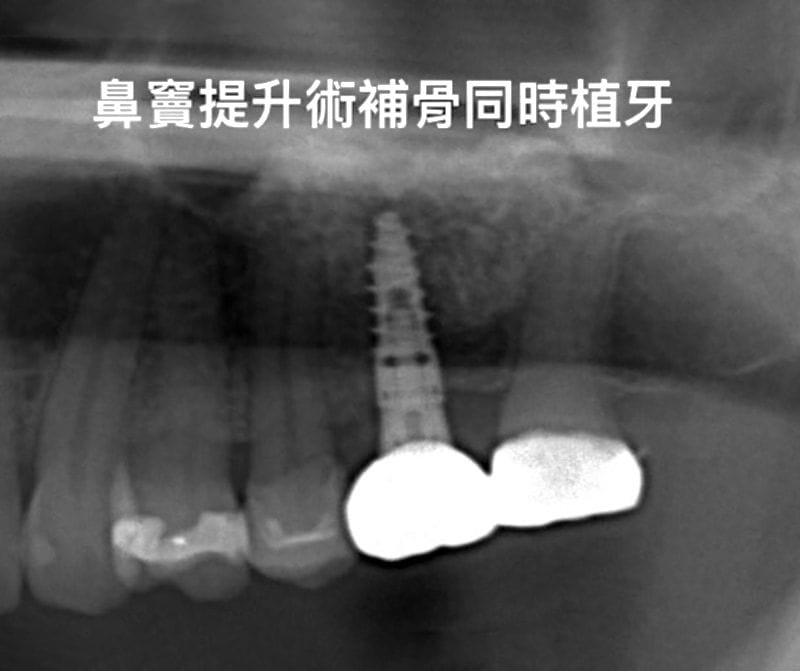

牙周治療完成後與開始重建後牙,由於左上區域的骨頭條件方面,高度比較不足,因此建議植牙手術時同時進行「側窗式鼻竇增高術」與補骨。

圖示:側窗式鼻竇增高術,箭頭為人工植牙處和側窗補骨粉處 圖示:補骨粉後覆蓋膠原蛋白再生膜,為牙周組織創造良好的再生復原空間

(上顎後牙區因骨質與骨量關係,植牙成功率一般而言較低。醫師會依照骨頭條件進行「側方開窗術」或「植牙孔處鼻竇增高術」來改善植牙條件。推薦可以參考 鼻竇增高術 – 上顎區植牙補骨法 進一步了解鼻竇增高術和手術後注意事項。)

我們等待上顎半年、下顎三個月人工植牙骨整合的時間後,順利地把正式假牙完成。

圖示:植牙完成後裝上正式假牙的X光片 圖示:鼻竇增高術、補骨與植牙手術後,人工植體周圍骨頭狀況穩定